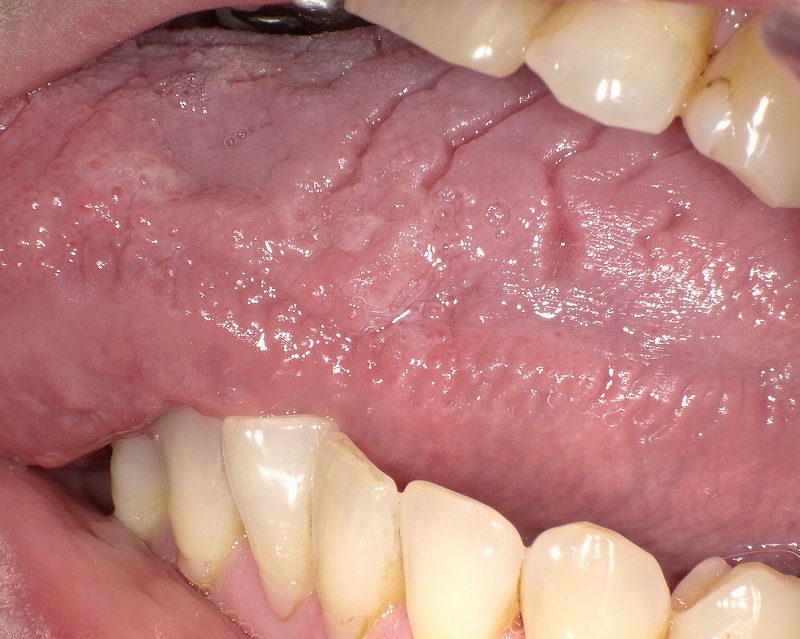

溝状舌。

溝状舌 - ひぐち歯科、口腔外科・口腔内科メディカルインフォメーション。

舌に溝がある これって大丈夫?溝状舌の正体と対応法。

舌の表面に多くの深いシワ、溝が発生して舌が割れてしまったように見える状態を溝上舌と言います。 溝上舌はほとんど先天的なもので生まれつき舌にひび割れがみられる方は治療の必要がない場合が多いです。カンジタ症、ウイルスなどの感染、外傷、ビタミン不足、ドライ。

溝状舌についてスタッフブログ。

溝状舌 こうじょうぜつ とは 溝状舌の痛みの原因と対処法。

溝状舌 Fissured Tongue の原因と治療法。

舌の表面に多くの深いシワや溝が形成されてしまう状態のことを溝上舌と呼びます。 溝上舌の溝の深さは様々で刺激物が染みやすく痛みや味覚の異常が出る場合があります。また舌に溝があるため汚れが溜まりやすく口臭を引き起こしやすいです。 炎症など起こさないように。